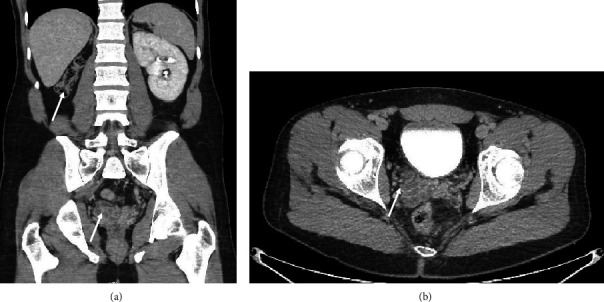

Zinner syndrome is a rare congenital anomaly characterized by a triad of renal dysgenesis/agenesis, cysts in the ipsilateral seminal vesicle, and ejaculatory duct obstruction. Though often diagnosed in infancy, the diagnoses can be incidentally found in adults who present with nonspecific genitourinary symptoms including dysuria, ejaculatory dysfunction, or genital pain. We present an unusual case of a 29-year-old male patient who presented to the emergency department with recurrent testicular pain and hematospermia and was found to have an atrophic right kidney with an ectopic ureter implanting into a cystic seminal vesicle. These findings were consistent with a rare subvariant of Zinner syndrome only previously described four times in the literature. We performed a robotic-assisted laparoscopic ectopic nephroureterectomy with sparing of his seminal vesicle. To our knowledge, this is the first report to describe the safe and effective use of robotic surgery in this setting to remove affected anatomy while preserving the patient's seminal vesicle.